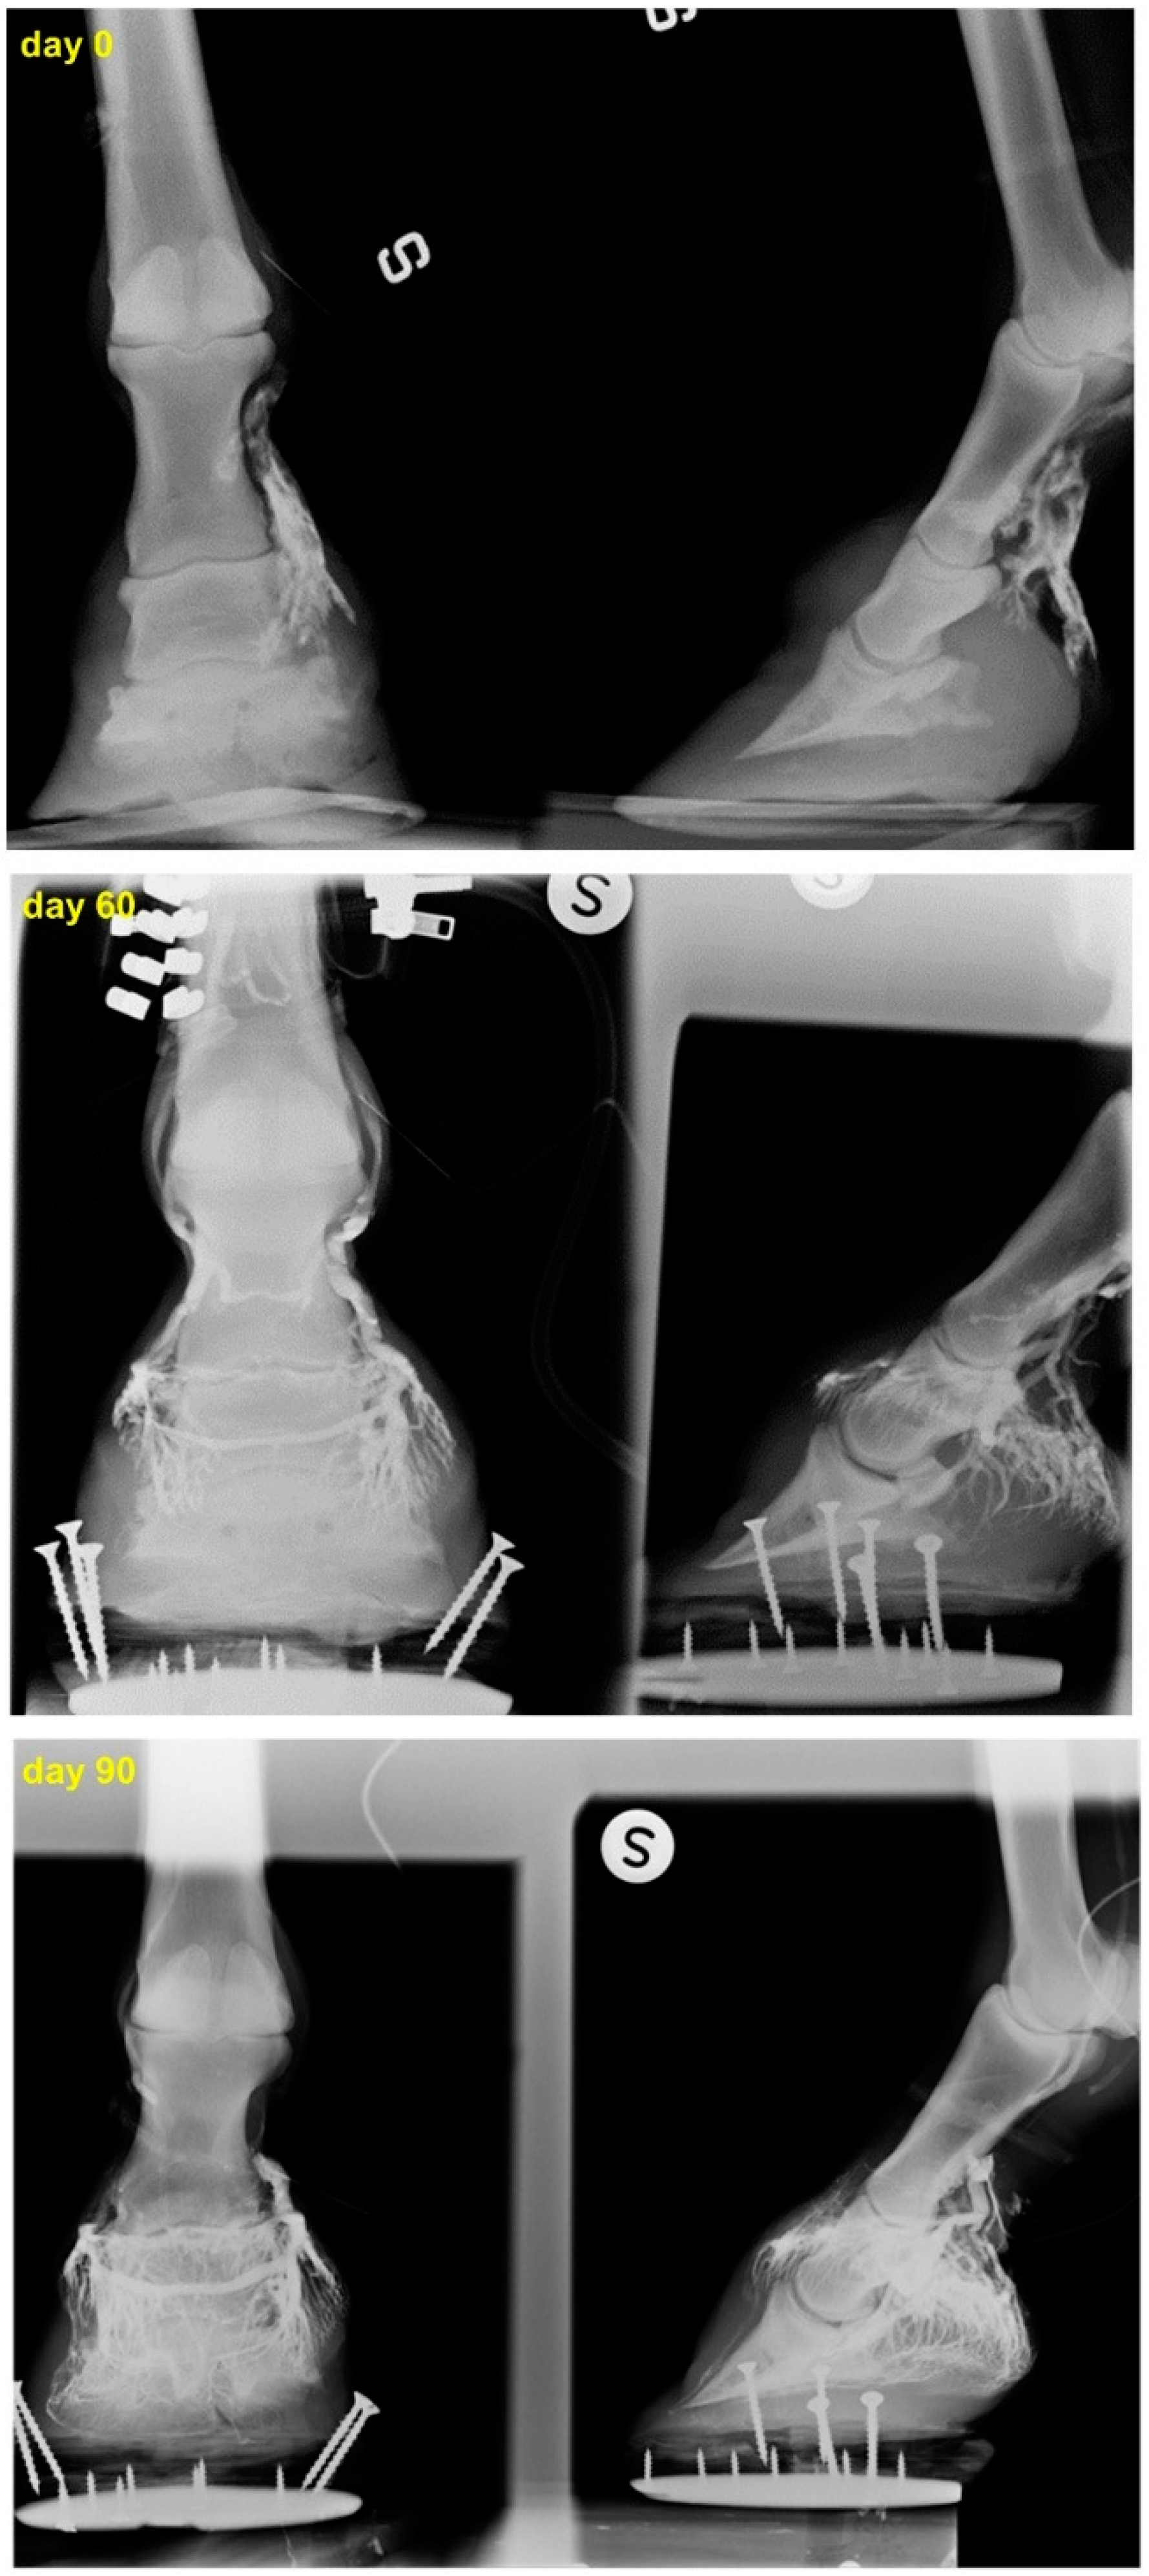

2.4. Efficacy and Outcome of the Therapy